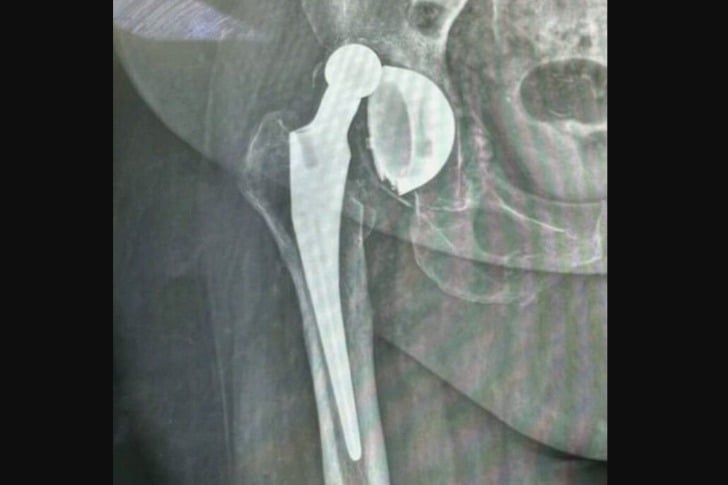

#21 Aquela “bola” deveria estar DENTRO do encaixe do quadril.

Isso pode acontecer após uma substituição de quadril se você não seguir as instruções sobre mantê-lo elevado e não estender demais a articulação por um período de tempo. Também pode acontecer como resultado de uma queda algum tempo depois.